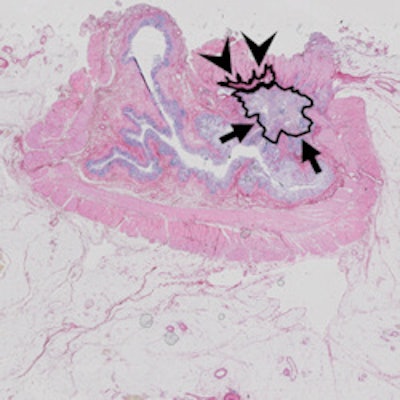

Same case as above. Histopathology confirmed the areas of residual tumor (arrows) and fibrosis (arrowheads).